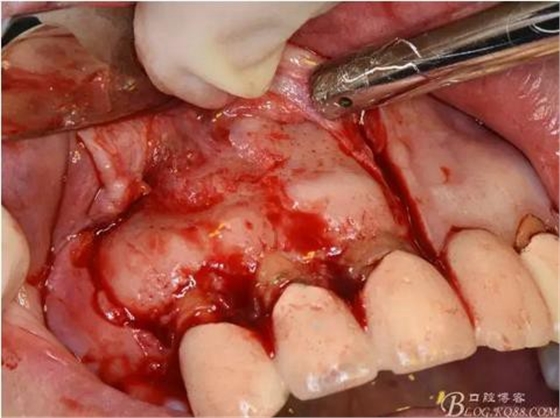

圖8.翻開梯形瓣

圖9.去除唇側(cè)薄的骨壁,暴露出囊壁